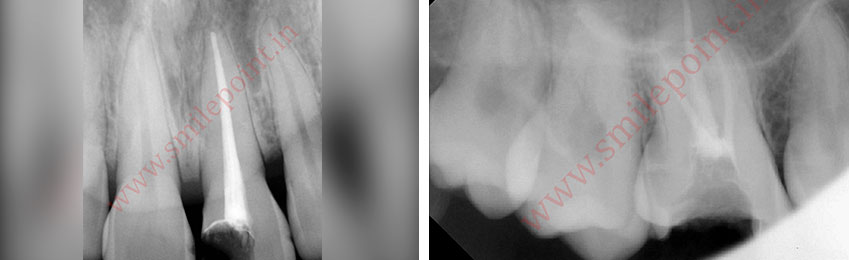

Computer Assisted Root Canal Treatment